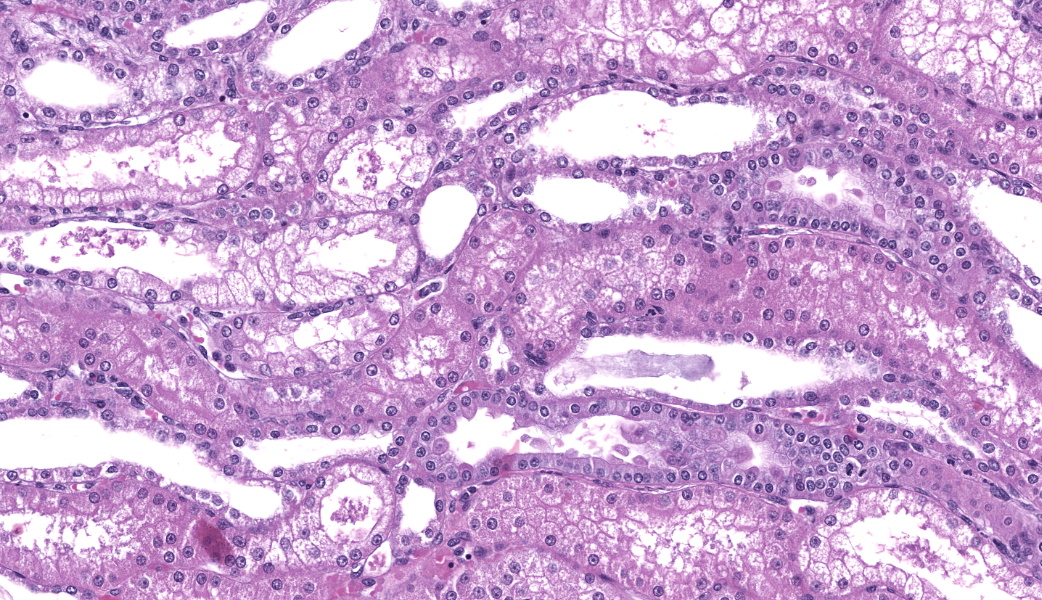

Renal lesions involve primarily the tubular component and are characterized by a variety of morphological features. Swelling and vacuolar change are prominent within proximal renal tubular epithelium, especially in the straight portion of that segment. Many tubules contain prominent cast-structures, typically consisting of granular to globular eosinophilic material, frequently admixed with blueish-gray proteinaceous sheets. Exfoliated epithelial cells are occasionally incorporated into the cast structures with numerous tubules also containing aggregates of mixed, primarily granulocytic inflammatory cells. Individually necrotic renal tubular epithelium is occasional evident. Associated with obstruction created by these casts, there is extensive, widespread tubular dilatation. Although extremely infrequent, fibrin thrombi were noted within occasional glomerular capillary loops. However, other significant glomerular changes were uncommon at the light microscopic level.

1. Renal tubular vacuolization, patchy to focally extensive, primarily proximal tubules, moderate-marked.

2. Coarsely granular eosinophilic tubular casts with occasional proteinaceous sheets consistent with myoglobin and associated myoglobinuric nephrosis, patchy, moderate, with associated marked tubular dilatation and epithelial cell thinning.

3. Acute tubular injury (ATI), patchy, mild, characterized by renal tubular epithelial cell exfoliation, individual cellular degeneration and patchy, primarily granulocytic inflammatory cell aggregates.

4. Focal glomerular capillary loop fibrin thrombi, minimal.

Renal casts noted in this case (and often admixed with numerous dehisced epithelial cells) were suggestive of myoglobin origin. They are often comprised of round granules that line up in chains or aggregate in clusters. Tinctorially, there is variation between and even within different stains applied with a typical pink to red-brown appearance with H&E, pink to bright magenta with PAS, and often a gray-blue sheet containing fine red granules on Trichrome.5,8 Immunostaining with antibody to myoglobin was strongly positive in these casts, often with a prominent rope-like string to beaded appearance. Interestingly, the concept that acute kidney injury is triggered by myoglobin as a direct, sole toxin appears to be oversimplified and there is ample evidence that additional factors such as hypovolemia, renal vasoconstriction or urine acidification are required for nephrotoxicity.9,12 Of these factors, certainly vasoconstriction directly associated with CNI effects would have likely been present. Again, in this case the myoglobinuric nephrosis present cannot be definitively ascribed to tacrolimus, but this is considered a likely pathogenesis, especially in the absence of other common pathogeneses such as severe trauma, dehydration, and other frequently associated comorbidities.5

The contributor of this case provided an exceptional comment and covered much of what was discussed in conference. Hemoglobin and myoglobin were discussed as the two main rule-outs for the granular casts present in the kidney and special attention was drawn to the fact that, with tacrolimus toxicity, the vacuolation of the straight portion of the proximal convoluted tubules (PCT) is the primary process and is associated with dilation of the smooth endoplasmic reticulum of the PCT epithelial cells.14 This kidney presented a couple of nice examples of tubular regeneration as well. Additional ruleouts in this case that were considered were aminoglycoside toxicity, which tends to appear more like a lysosomal storage disease with build-up of cytoplasmic material in the PCT epithelial cells, mannitol administration, which can cause osmotic nephrosis when given in high volume or over a prolonged period of time, and any other toxins that inhibit CYP450 that may have also resulted in tubular epithelial vacuolation.